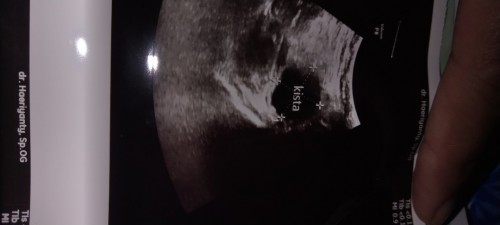

Apakah kista Di saat Hamil Berbahaya😭

Kadang rasa ngilu